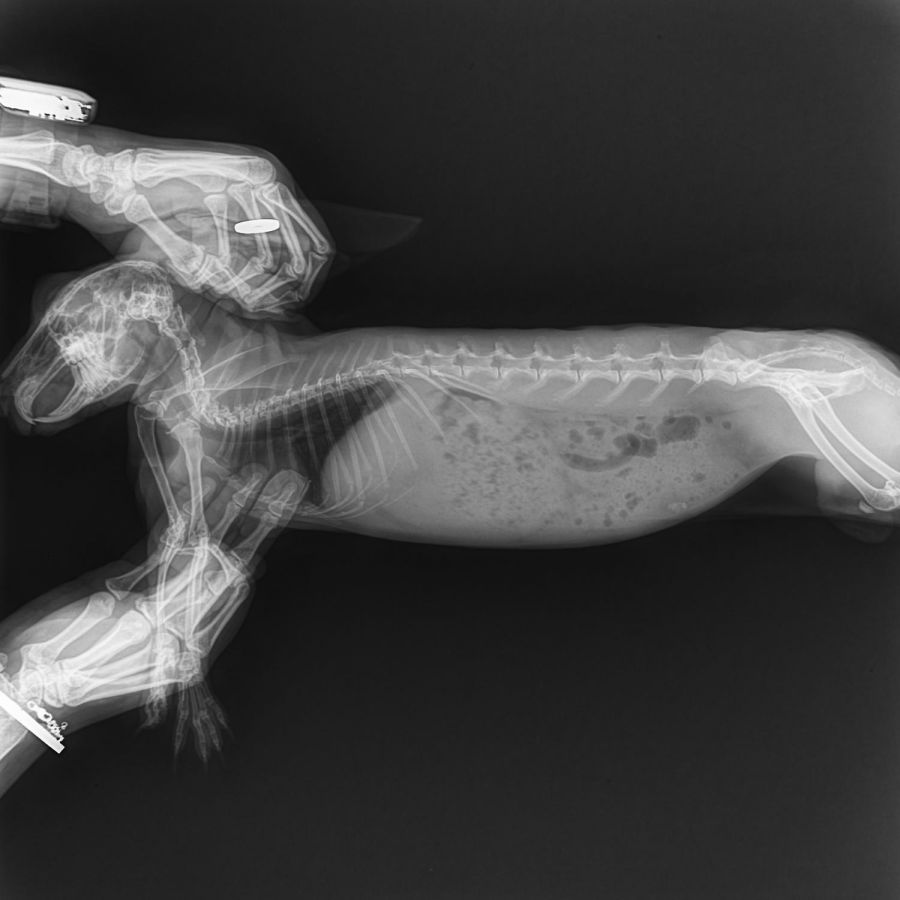

Recently, Shogun suddenly became ill, showing symptoms such as loss of appetite, difficulty passing stool, and signs of pain. After veterinary examination, he was diagnosed with liver torsion, a life-threatening emergency condition in rabbits that requires urgent surgery by a specialist. Without timely treatment, his life is at serious risk.